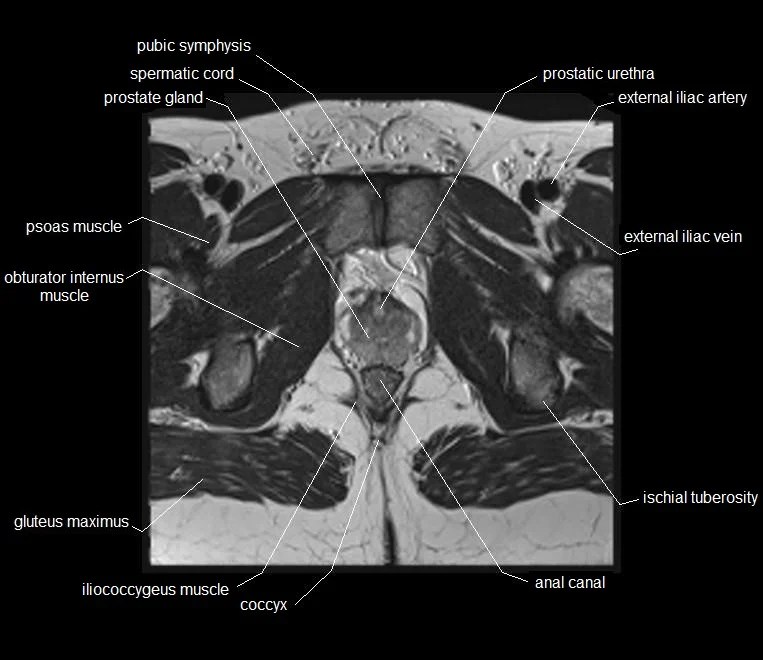

Mri Anatomy Male Pelvis . Anatomy of the male pelvis (prostate, bladder, genital organs, perineum) on mr imaging, male pelvis, mri, urinary system. Mri techniques for imaging the male pelvis; Knowledge of normal pelvic anatomy on mri is critical for proper interpretation, in particular the standard visceral organ appearances, commonly encountered variants, and. The gonadal vessels refer to the testicular artery and testicular vein in males and the ovarian artery and ovarian vein in females. This article reviews normal male pelvic floor anatomy and how it differs from the female pelvis; Radiologists have historically imaged the male pelvis using many methods. This webpage presents the anatomical structures found on male pelvis mri. Penis, testis, prostate, urinary bladder. This mri male pelvis axial cross sectional anatomy tool is absolutely free to use. Use the mouse scroll wheel to move the images up and.

Knowledge of normal pelvic anatomy on mri is critical for proper interpretation, in particular the standard visceral organ appearances, commonly encountered variants, and. Penis, testis, prostate, urinary bladder. Mri techniques for imaging the male pelvis; Use the mouse scroll wheel to move the images up and. This article reviews normal male pelvic floor anatomy and how it differs from the female pelvis; Anatomy of the male pelvis (prostate, bladder, genital organs, perineum) on mr imaging, male pelvis, mri, urinary system. This mri male pelvis axial cross sectional anatomy tool is absolutely free to use. The gonadal vessels refer to the testicular artery and testicular vein in males and the ovarian artery and ovarian vein in females. Radiologists have historically imaged the male pelvis using many methods. This webpage presents the anatomical structures found on male pelvis mri.

Mri Anatomy Male Pelvis This article reviews normal male pelvic floor anatomy and how it differs from the female pelvis; This webpage presents the anatomical structures found on male pelvis mri. Use the mouse scroll wheel to move the images up and. Anatomy of the male pelvis (prostate, bladder, genital organs, perineum) on mr imaging, male pelvis, mri, urinary system. This article reviews normal male pelvic floor anatomy and how it differs from the female pelvis; The gonadal vessels refer to the testicular artery and testicular vein in males and the ovarian artery and ovarian vein in females. Radiologists have historically imaged the male pelvis using many methods. This mri male pelvis axial cross sectional anatomy tool is absolutely free to use. Mri techniques for imaging the male pelvis; Penis, testis, prostate, urinary bladder. Knowledge of normal pelvic anatomy on mri is critical for proper interpretation, in particular the standard visceral organ appearances, commonly encountered variants, and.